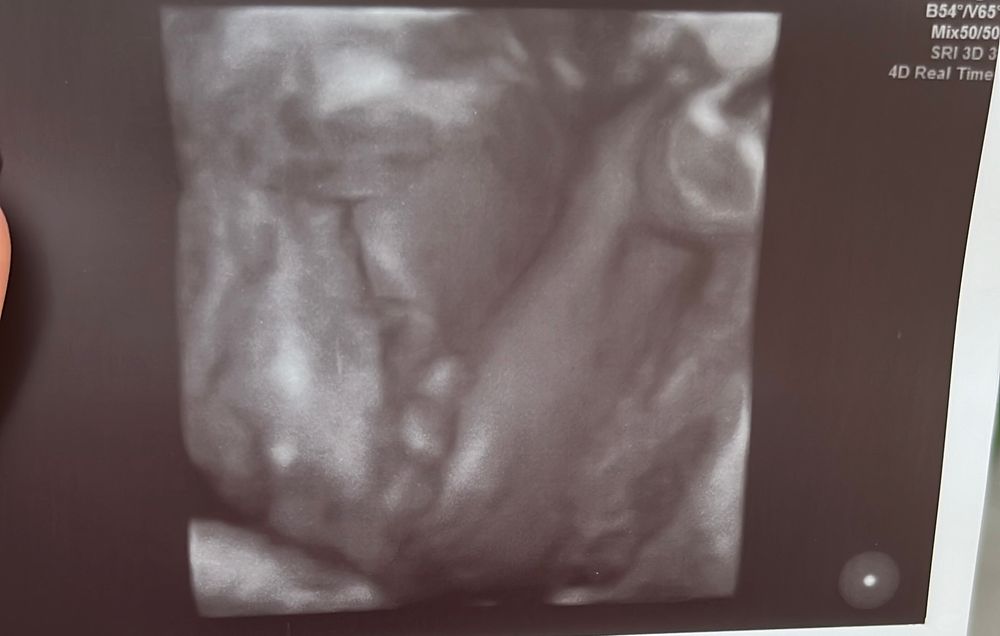

сегодня была на втором скрининге 21 неделя,сказали у вас 100% мальчик

2 мальчик